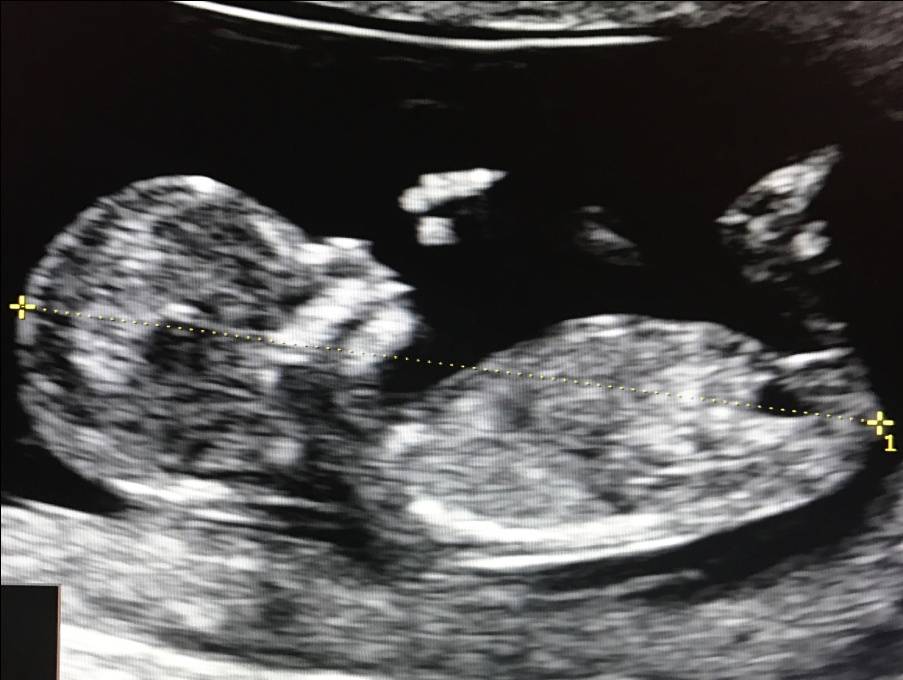

1. Копчико-теменной размер (КТР) плода

Этот показатель точно определяет срок гестации (беременности), особенно в случае, если женщина не помнит 1-й день последней менструации, либо если менструальный цикл у нее не регулярный. В заключении срок беременности выставляется по КТР плода, а не по дате последней менструации.

Правильное измерение КТР плода

2. Маркеры хромосомной патологии:

– толщина воротникового пространства (ТВП) – является основным признаком хромосомной патологии у плода. Патологической величиной считается увеличение ТВП больше 95-й процентили для каждого срока гестации. Каждое увеличение ТВП повышает риск существования хромосомной аномалии у плода.